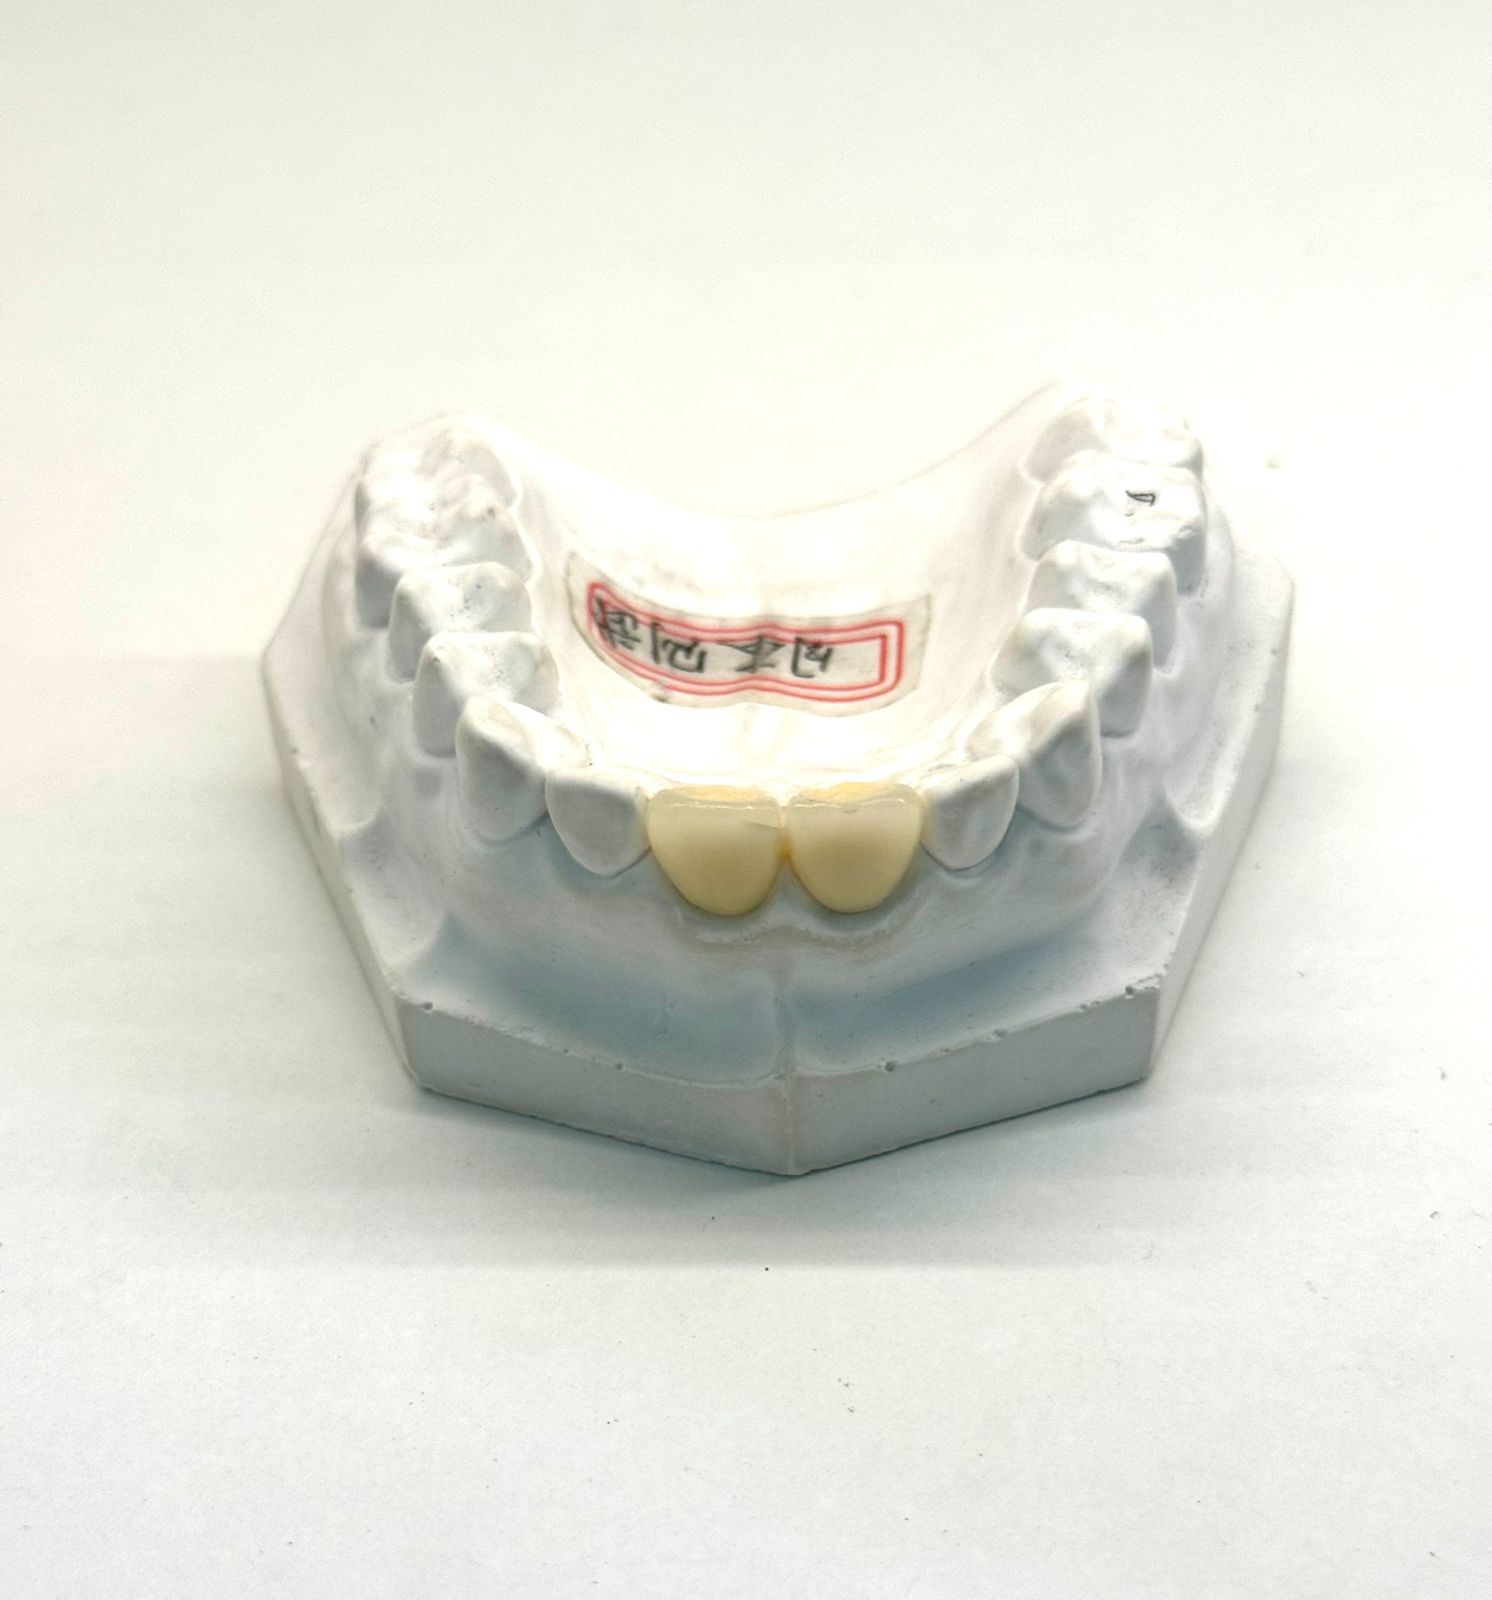

Примеры зубных коронок в Хуньчуне

Какие бывают коронки?

Коронки делают из разных материалов: есть более простые варианты и решения премиум-класса. Чтобы ориентироваться было проще, выделим самые востребованные направления.

В практике протезирование чаще всего опирается на два материала, которые уверенно держат первое место по сочетанию цены, прочности и внешнего вида: металлокерами и цирконий. Именно эти коронки выбирают чаще всего, поэтому дальше логично сравнить их между собой.

Кому подходят: Зубные коронки подходят, если зуб сильно разрушен кариесом или сколом, после лечения каналов стал хрупким, есть трещины или выраженная стираемость. Их ставят, чтобы восстановить форму и жевательную функцию, улучшить эстетику при потемнении и дефектах, а также при протезировании — на имплант или как опору под мост, включая замену старых изношенных коронок.